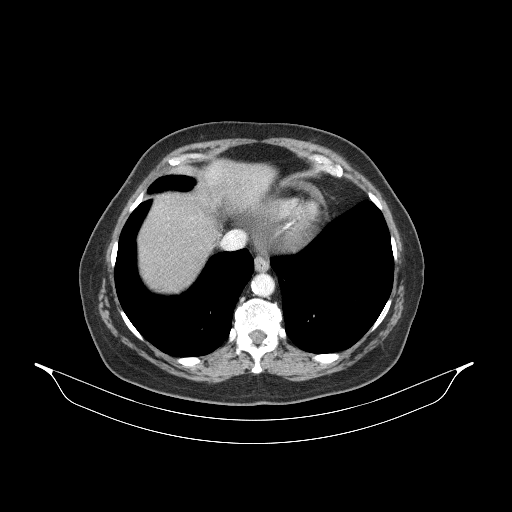

Generated VENOUS CT scan (A→B translation)

Mediastinum window (WL 40, WW 400 β†’ Low βˆ’160, High +240)

Actual HU range: [-160.0, 240.0]